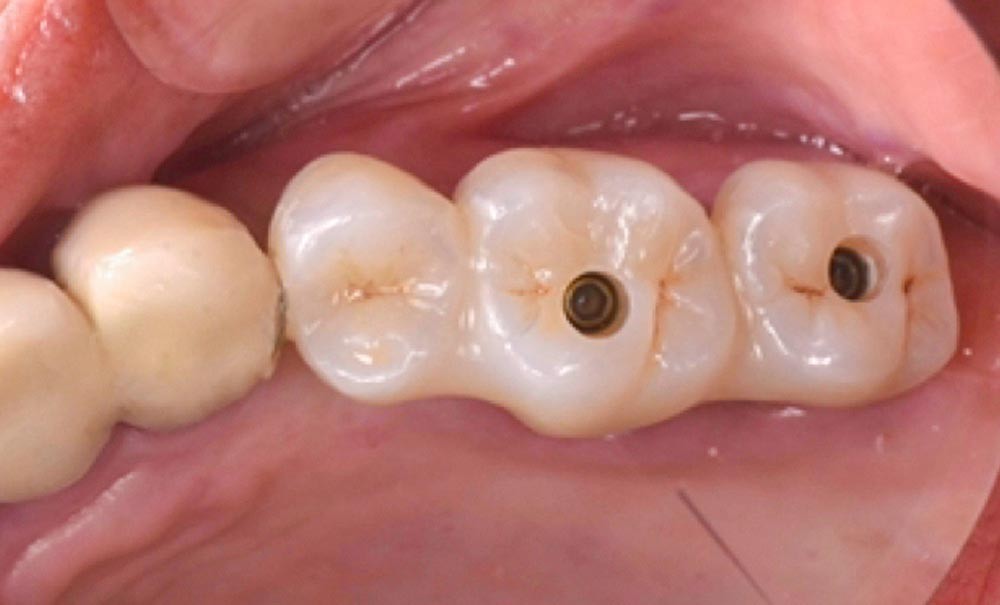

La patiente étant réticente à une chirurgie d’augmentation osseuse et non motivée à réduire sa consommation tabagique, nous avons privilégié l’option de deux implants en extraction-implantation-immédiate (EII) sur 26 et 27, avec un bridge céramique de 3 éléments avec extension mésiale en 25.

L’intervention chirurgicale s’est déroulée selon les étapes suivantes (fig. 2) :